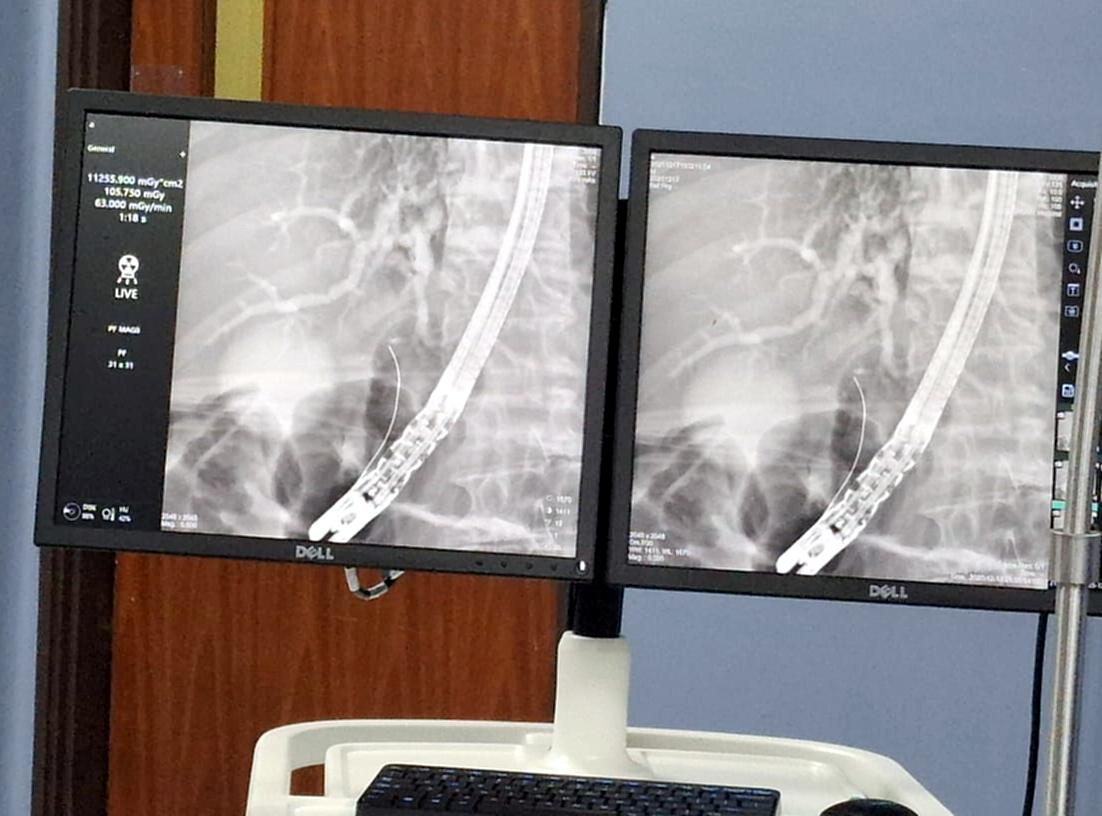

Ayer miércoles 17 de diciembre, el Hospital de Especialidades Quirúrgicas Ingavi realizó por primera vez una Colangiopancreatografía Retrógrada Endoscópica (CPRE), incorporando así este procedimiento avanzado como parte de su capacidad diagnóstica y terapéutica para pacientes de alta complejidad.

La CPRE es una técnica que combina endoscopía y fluoroscopía, y permite el diagnóstico y tratamiento de patologías de la vía biliar y pancreática, como litiasis, estenosis, obstrucciones tumorales y otras afecciones que requieren intervenciones especializadas. El procedimiento se realiza mediante la introducción de un endoscopio flexible hasta el duodeno, con inyección de medio de contraste y la posibilidad de realizar maniobras terapéuticas como extracción de cálculos o colocación de prótesis.